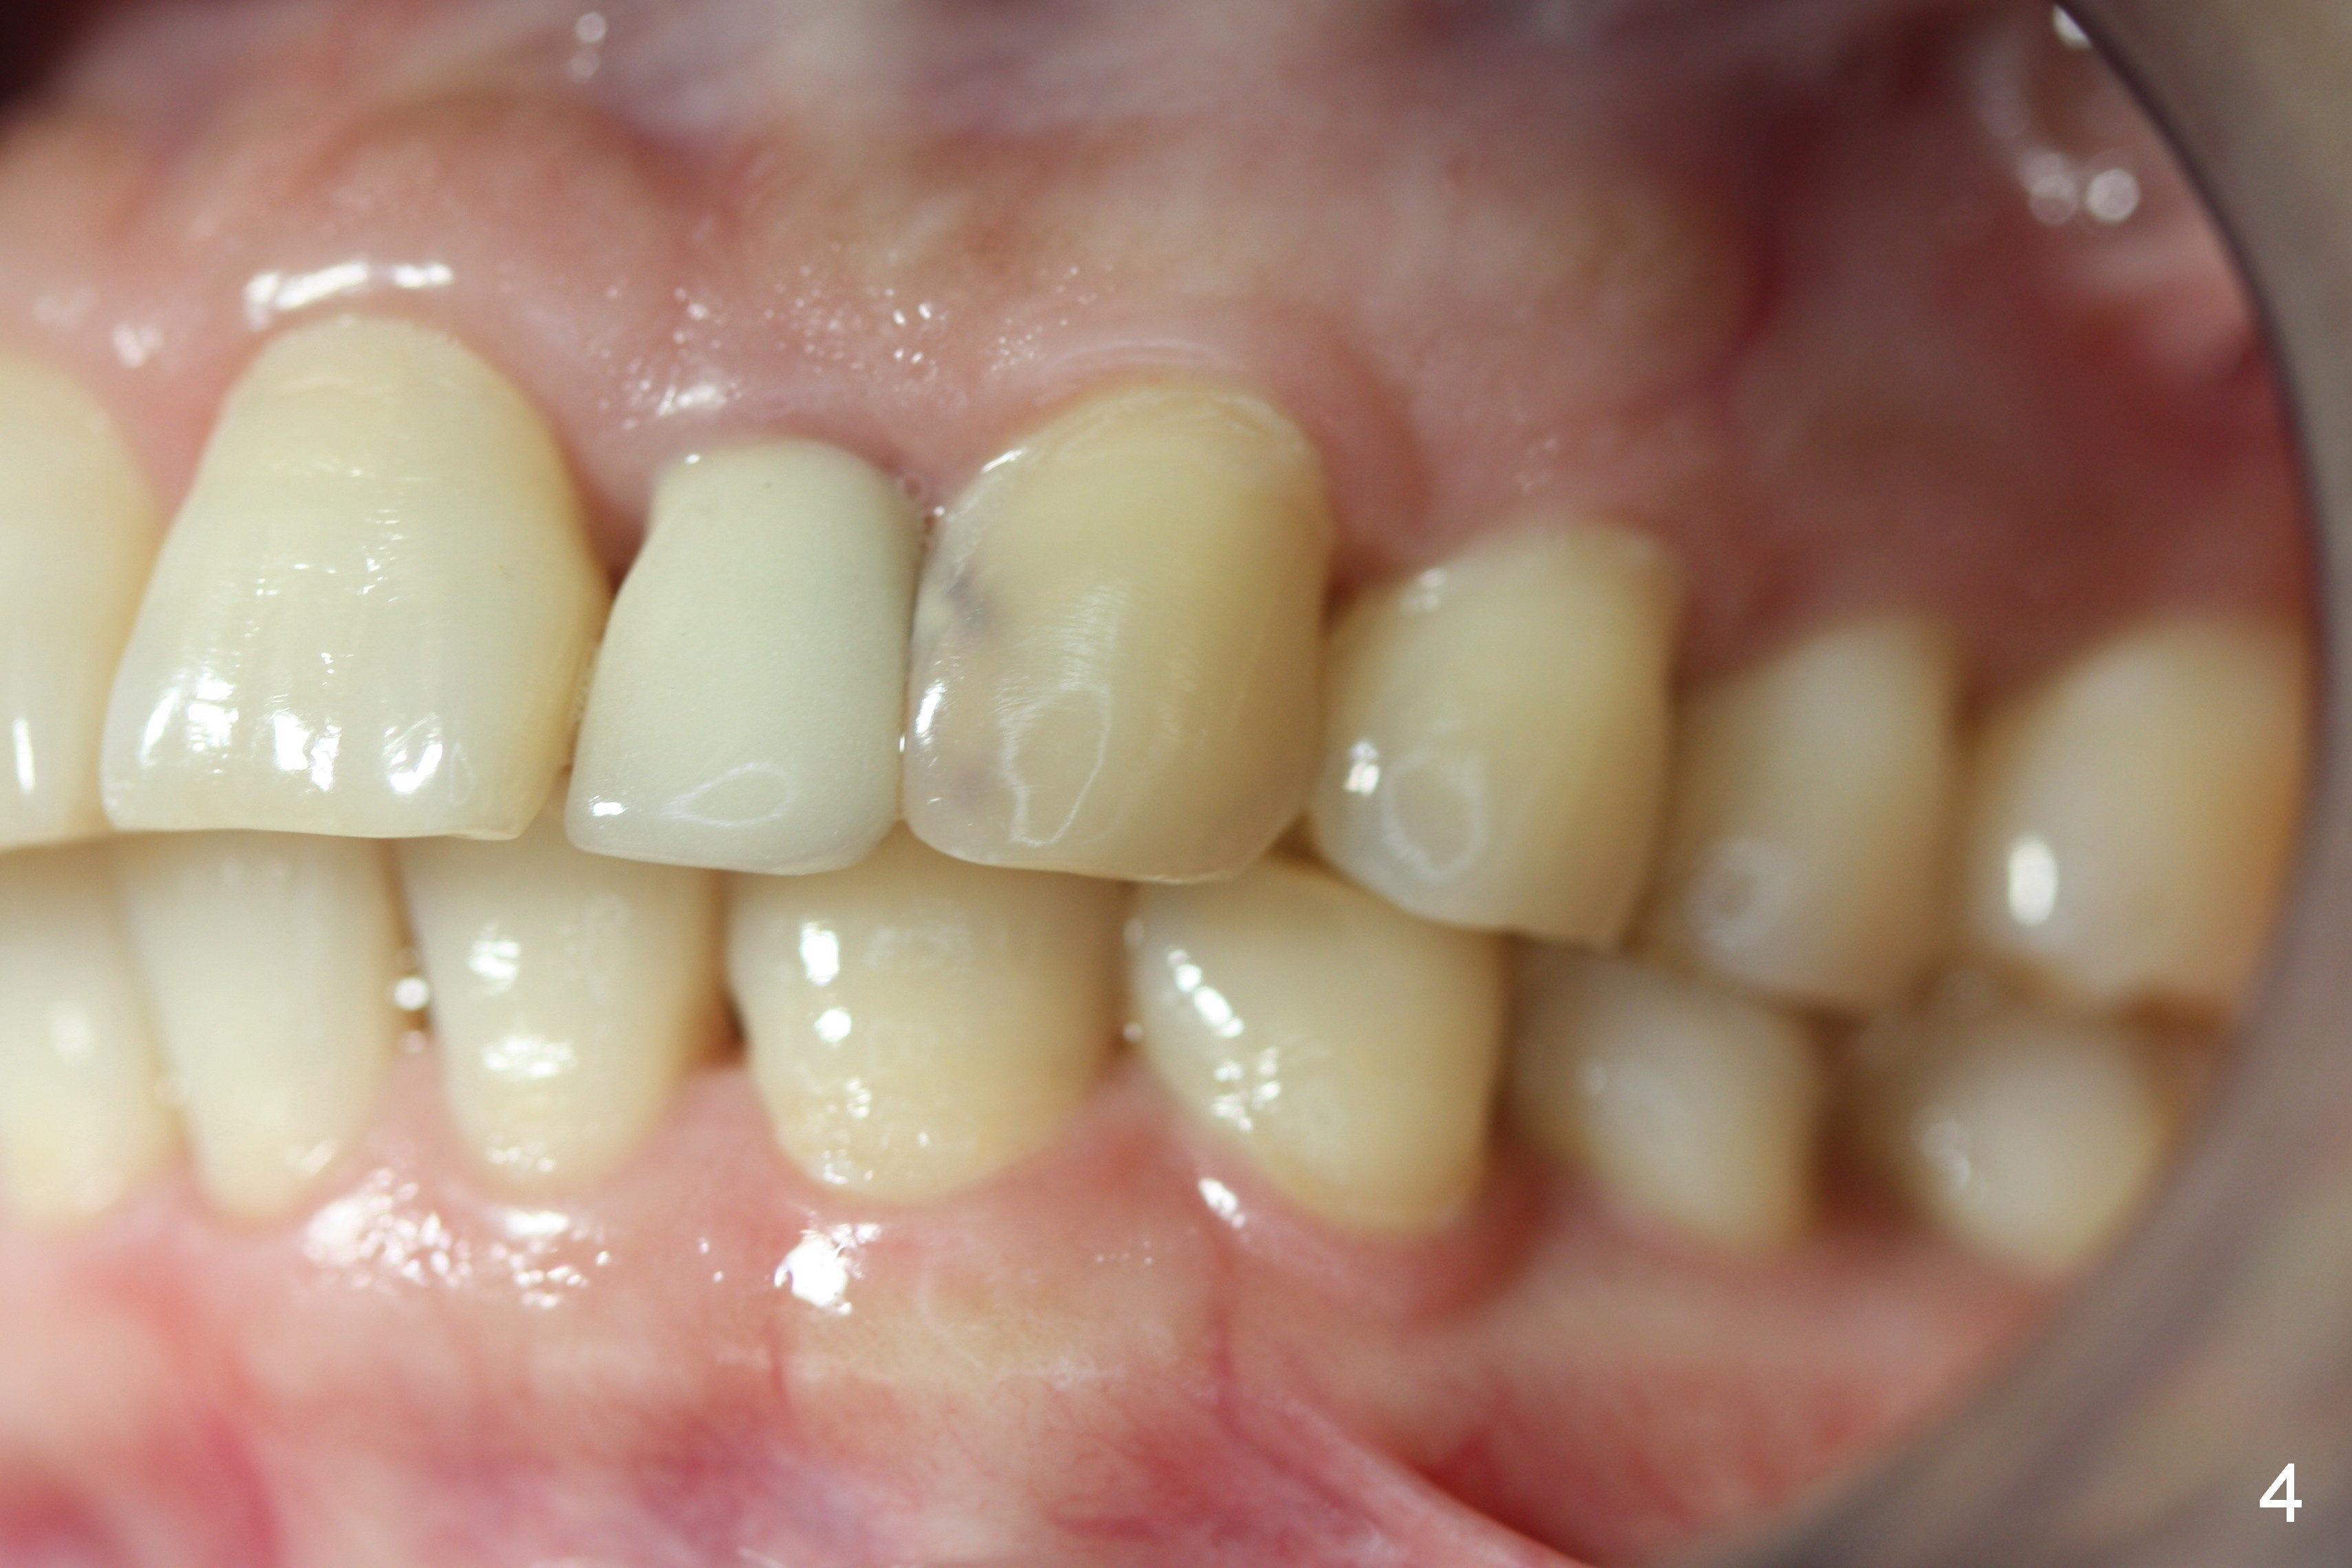

A 53-year-old woman wants to improve tooth appearance. Her concerns include microdontia at UR, UL 2 and caries at UL 3. The upper dental midline deviates to the left (Fig.1), while the lower one to the right (Fig.2). This may be related to unilateral Class II malocclusion (Fig.3,4).